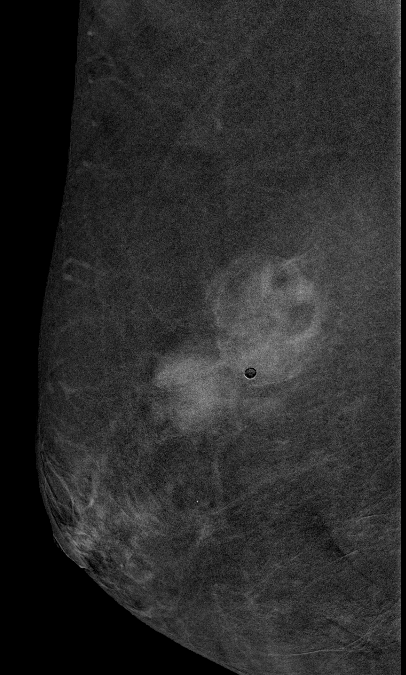

• Mujer de 35 años, sin antecedentes médicos de interés. No hábitos tóxicos. No toma tratamiento crónico. Colecistectomizada como único antecedente quirúrgico. • Ingresa para estudio de epigastralgia de un mes de evolución. No fiebre. Analíticas con elevación de...